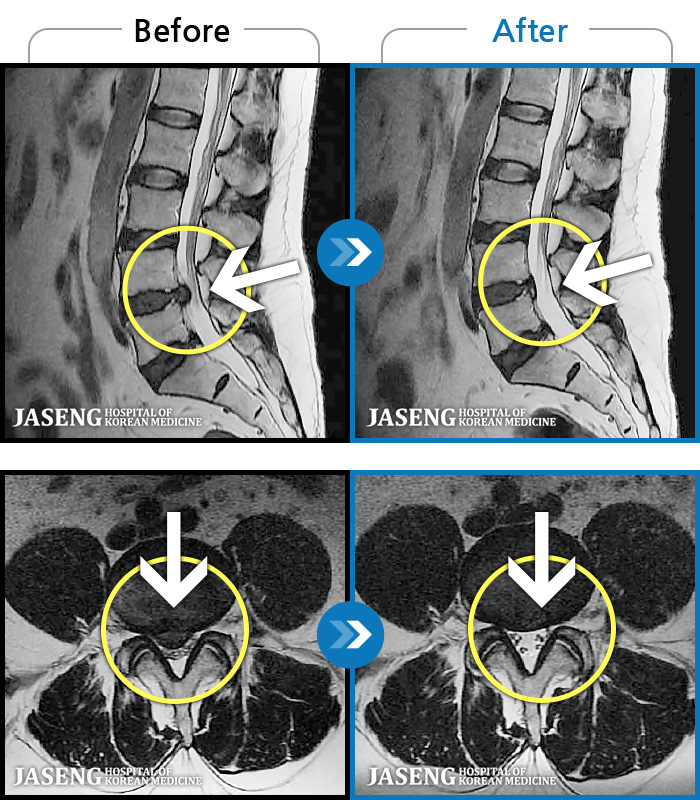

1,240 MRI ũ ʸ Ȯϼ.

MRI ġ

Ƹ ϰ ־.